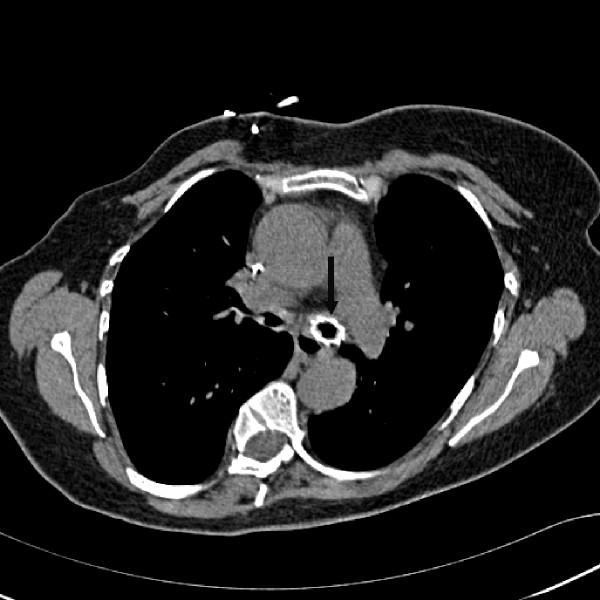

The use of cardiopulmonary bypass as an adjunct to airway surgery for non-malignant diseases in adults is not well established in the UK. We are reporting two cases which demonstrate the additional benefits of using cardiopulmonary bypass during difficult bronchoscopy and complex airway stenting. The first case presents an emergency indication for cardiopulmonary bypass in a life-threatening but benign condition. The second case presented, utilises cardiopulmonary bypass standby as adjunct to a potentially life threatening procedure. A review of the literature is also provided.

在英国,将体外循环作为成人非恶性疾病气道手术的辅助手段尚未得到充分确立。我们报告两例病例,展示了在困难支气管镜检查和复杂气道支架置入过程中使用体外循环的额外益处。第一例病例呈现了在危及生命但为良性病症中体外循环的紧急指征。第二例病例利用体外循环备用作为对潜在危及生命手术的辅助手段。同时还提供了文献综述。